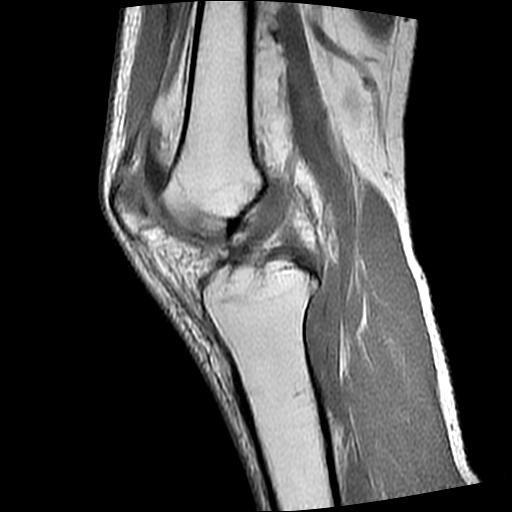

40岁男性,右膝关节外伤,x光平片示,髁间隆突撕脱骨折。

1、前交叉韧带撕裂;

2、外侧半月板后角撕裂;

3、关节腔积液。

前交叉韧带撕裂,关节腔积液.

半月板1-2级损伤   前交叉韧带撕裂伤   关节腔少量积液  诸骨未见新鲜外伤性改变

髁间隆突撕脱骨折;内侧副韧带损伤。

1、内侧副韧带撕裂;

2、前交叉韧带撕裂;

3、滑膜炎伴关节腔积液。

内侧副韧带撕裂及关节腔积液是肯定的,但是前交叉撕裂确定吗?会不会有容积效应的因素,因为前一张前交叉显示清楚,连续性良好,且较光滑。请问楼主有关节镜支持吗?我们医院也经常有这样的患者,但苦于没有关节镜,而无法对照、证实(除非完全断裂),出现了不同的诊断结果只能毫无意义的争论。

1、前交叉韧、内侧副韧带撕裂;

3、关节腔积液。4、髁间脊撕脱骨折。

除了关节积液外并无韧带撕裂,acl胫侧附着点有2束,正常情况下脂肪信号。此病例应加做压脂像以便观察是否有骨损伤。